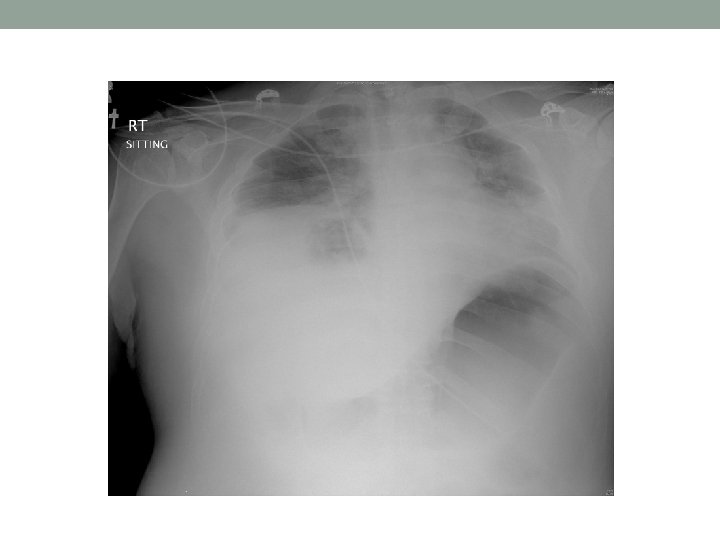

Day 9 • Clinically static • WCC still high(>20) • Low dose vasopressor still needed • CT abdomen: • Large collection in left retroperitoneal space • USG guided perinephric abscess drainage • Bloody aspirate yeilded • Culture: no growth

Progress • Further improvement • Extubated on day 12 • Dischargednto general ward on day 14 • In ward • BP/P stable • Refinement in glucose control • Physiotherapy • Planned discharge…